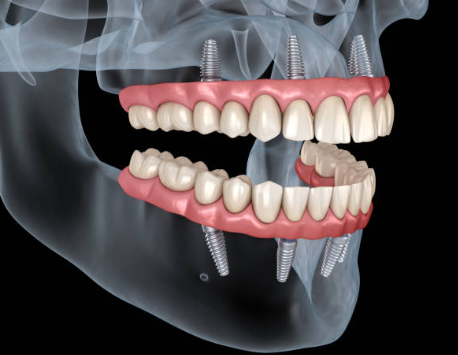

임플란트의 사전적 의미는 다음과 같습니다. 임플란트는 상실된 치아를 인공 치아 이식을 통하여 건강한 구강을 가지게 하는 의학 분야를 뜻합니다.

본래에는 인체의 조직이 상실되었을 때 이를 회복시켜 주는 대체 물질을 의미하지만, 치과에서는 인공 치아 이식의 의미를 지니기도 합니다. 이해를 쉽게 하기 위하여 다시금 말씀드리면, 인공적인 치아를 상실된 치아부위의 잇몸 뼈에 식립을 한 후, 그 위에 인공치아를 장착하여 수복하는 치료 방법을 말하는 것입니다.